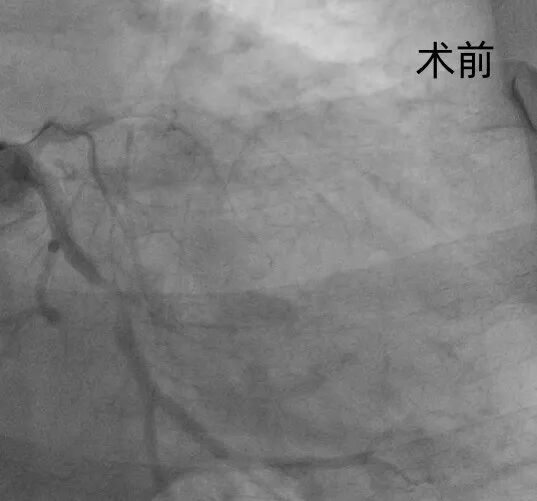

钟先生抵达医院后,直接送入导管室,冠脉造影清晰显示:前降支(LAD)近端完全闭塞,远端血流中断,心肌正处于“断供”坏死的危急状态。

心血管科团队当机立断,迅速实施PCI术,精准植入3枚支架,闭塞血管瞬间恢复通畅。从患者入院到血管成功开通,全程仅用46分钟,远优于国际指南60分钟的标准。